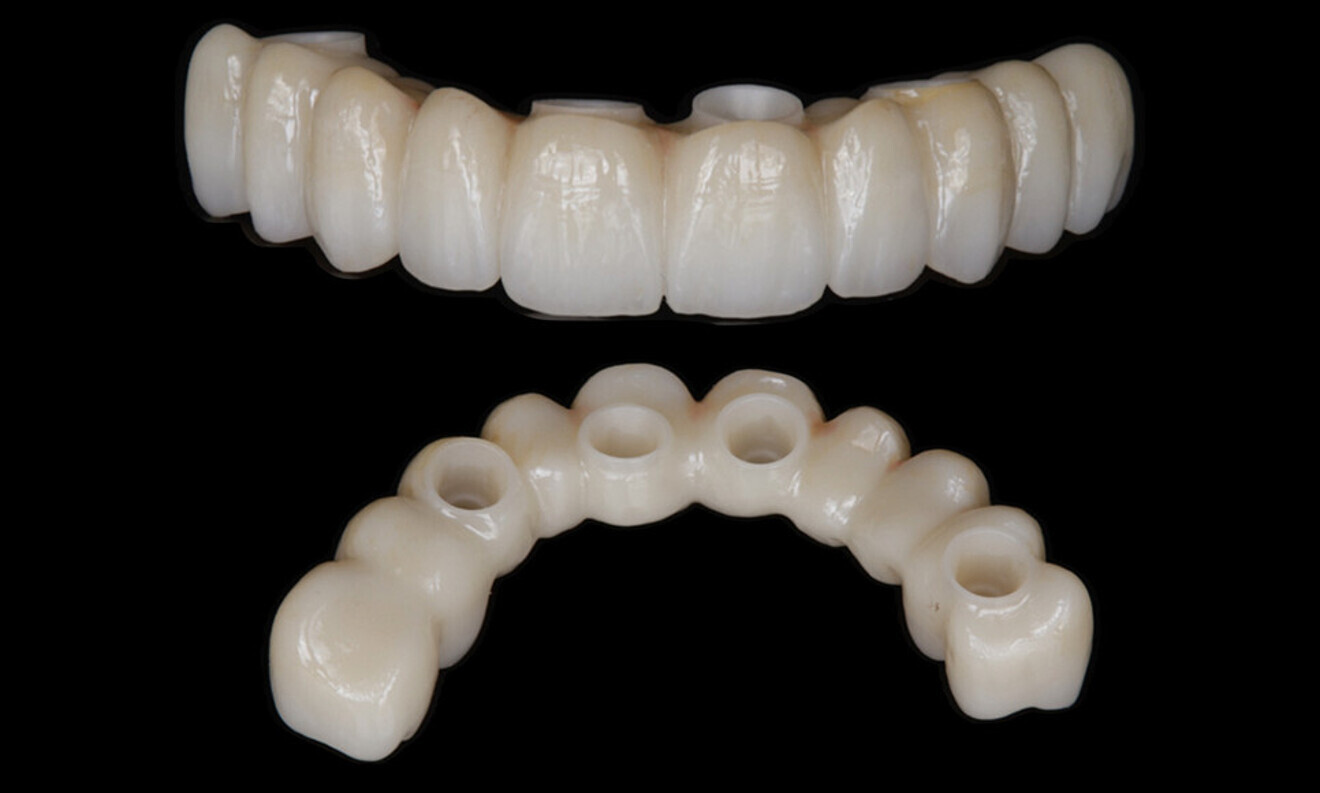

After a healing period of five months and successful osseointegration, the process for the definitive restorations was initiated. The chosen material was milled monolithic zirconia, and Variobase final abutments was used, placed on the screw-retained abutments to ensure excellent stability and retention of the definitive restorations (Figs. 69–75).

Figs. 69–75: The definitive restorations were fabricated after a five-month healing period